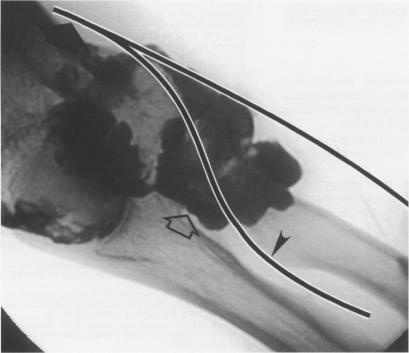

An uncommon cause of finger drop in a patient with rheumatoid arthritis.

Ann Rheum Dis. 1996 Oct;55(10):728-30. doi: 10.1136/ard.55.10.728.

Elbow arthrography in the evaluation of posterior interosseous nerve compression in rheumatoid arthritis.肘关节造影在类风湿性关节炎后骨间神经受压评估中的应用